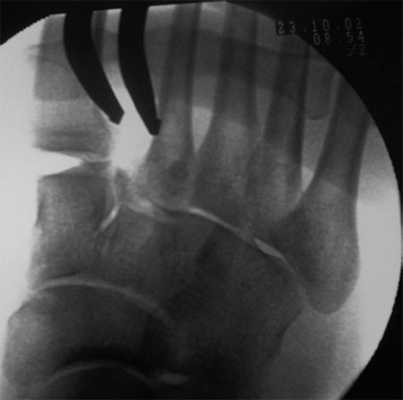

(Справа) На рисунке тыльной поверхности стопы изображен частичный переломовывих сустава Лисфранка. Первая плюсневая кость расположена правильно, в то время как 2-5 плюсневые кости смещены латерально. Связка Лисфранка разорвана. (Слева) При рентгенографии среднего отдела стопы в боковой проекции определяются вывихи 1-5 предплюсне-плюсневых суставов, ладьевидно-клиновидного сустава и сустава Шопара, возникшие у мотоциклиста в результате дорожно-транспортного происшествия. Кроме того, выявляется множество мелких костных фрагментов.

(Справа) У этого же пациента при рентгенографии среднего отдела стопы в передне-задней проекции лучше видны переломы плюсневых костей и деформация сустава Шопара. В этой проекции суставные поверхности 1-го предплюсне-плюсневого сустава выглядят конгруэнтными, однако наличие в боковой проекции расширения дорсальною отдела суставной щели свидетельствует о нестабильности сустава. (Слева) При рентгенографии среднею отдела стопы в передне-задней проекции определяется изолированный переломовывих 1-го предплюсне-плюсневого сустава: косой перелом основания 1-й плюсневой кости и ее подвывих. Кроме тою, выявляется перелом медиальной клиновидной кости. Этот переломовывих можно отнести к продольному типу.

(Слева) При рентгенографии стопы в боковой проекции определяется необычное для вывиха сустава Лисфранка смещение в подошвенную сторону 1-й и 2-й плюсневых костей. Травма была получена при полете на буксируемом парашюте.

(Справа) У этого же пациента при рентгенографии стопы в передне-задней проекции визуализируется одностороннее смещение оснований плюсневых костей. Наблюдаются переломы медиальной клиновидной кости и оснований 2-й и 3-й плюсневых костей. (Слева) При рентгенографии среднего отдела стопы в передне-задней проекции определяется изолированный медиальный вывих 5-й плюсневой кош. В норме шиловидный отросток 5-й плюсневой кости выступает латеральнее края кубовидной кош. Остальные предплюсне-плюсневые суставы выглядят интактными, что и было подтверждено при КТ.